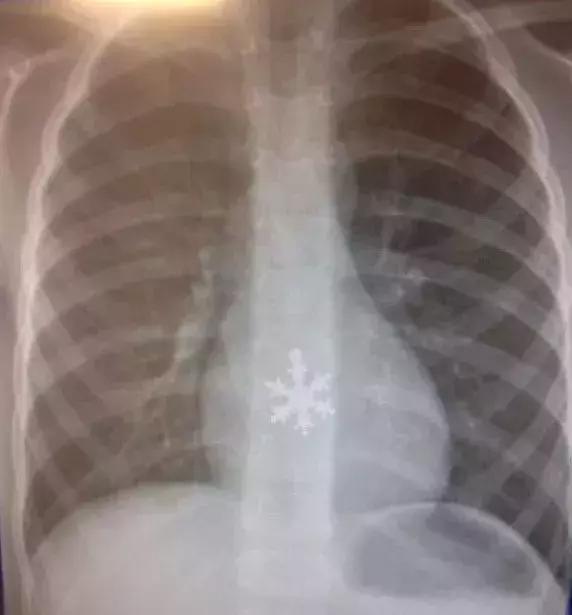

吞下的雪花状异物